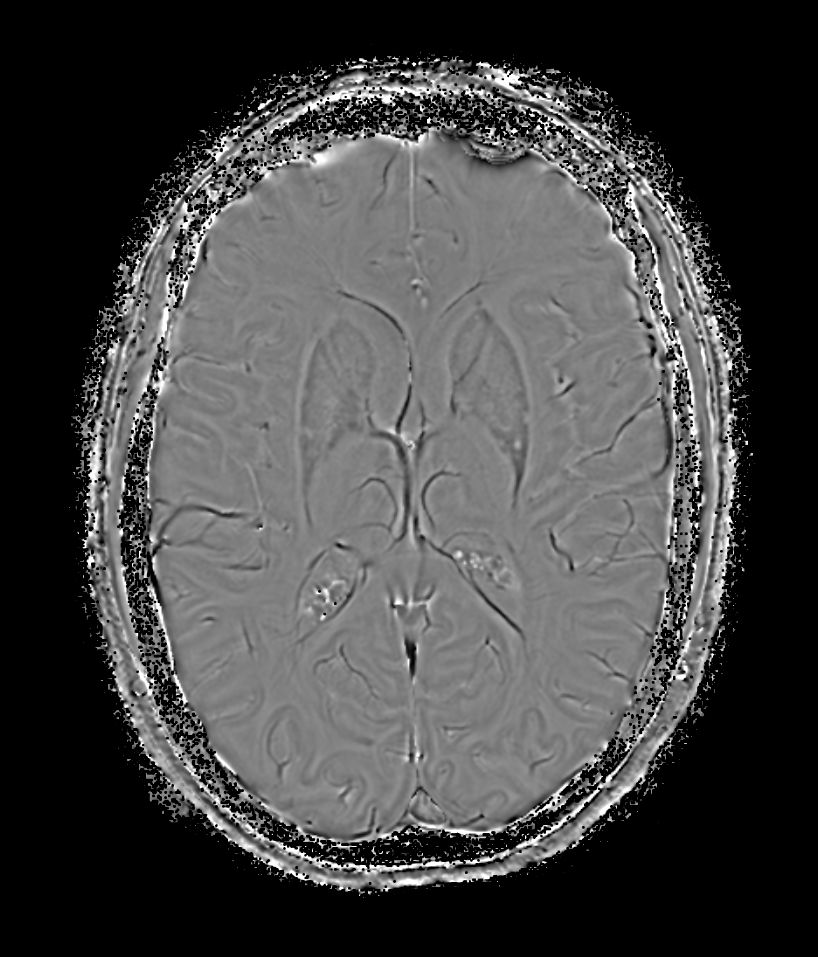

SWIp 6 echoes (Phase)